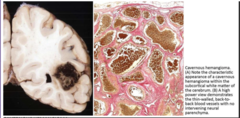

cavernous hemangioma(Second worst)

abnormally dilated blood vessels, back-to-back vessels, no intervening parenchyma. Mostly frontal-parietal. Intravascular thrombosis. purple malformation, "Raspberry" Large, cystically dilated, thin-walled vessels. simple endothelial lining. Thin fibrous adventitia(butter layer)